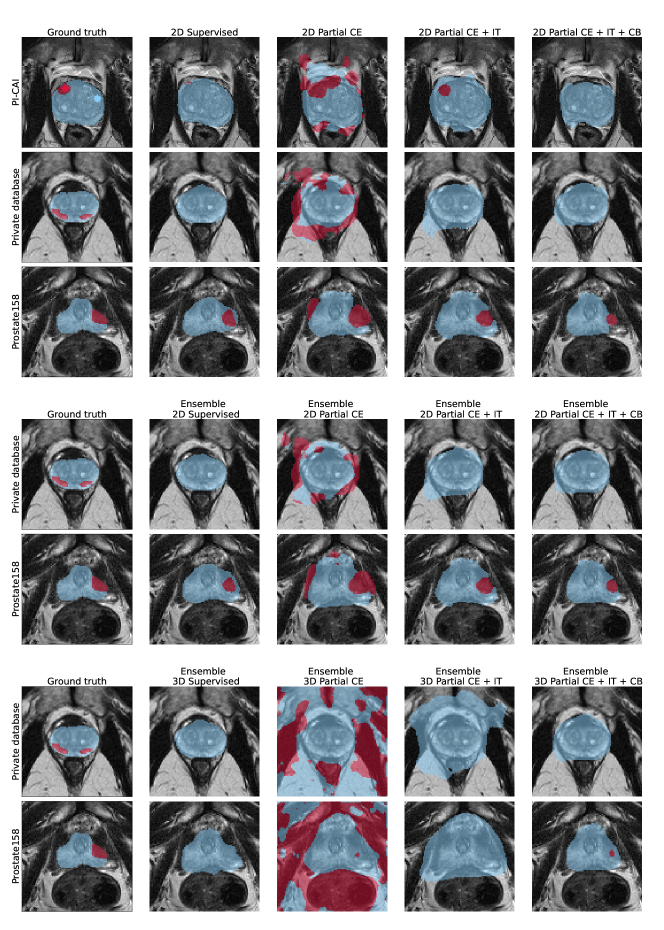

Figure 1 shows performance of all considered models for the three metrics of interest, namely sensitivity at 1 FP, AP and AUROC. Figure 3 provides examples of visual results of lesion detection maps for some 3D models. Extended visual results, including of 2D and ensemble models, are showcased in Appendix E.

Appendix E Supplementary visual results

Appendix G Model results for prostate segmentation